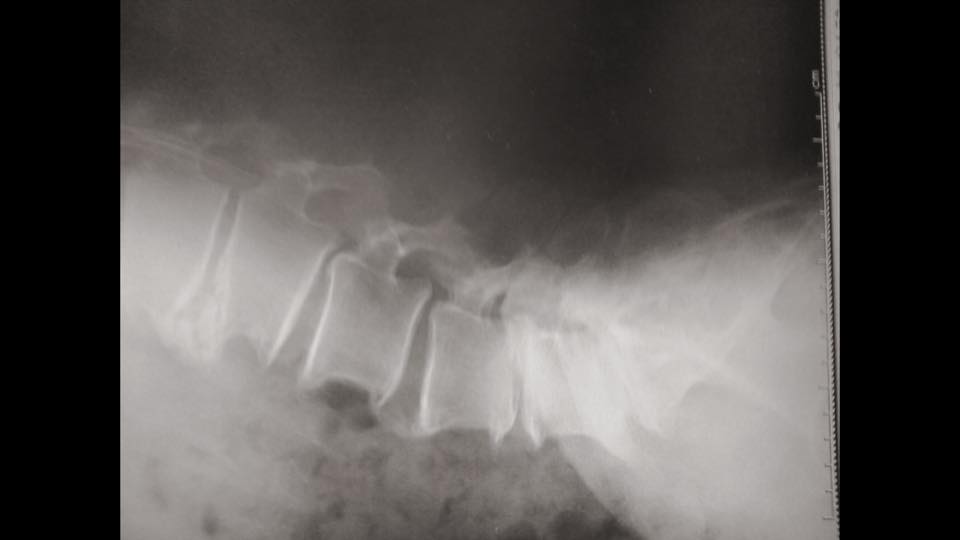

と言って持ってきたレントゲン写真を眺める。

「で、お医者さんはコレ見てなんて?」

「はい、分離滑り症とかで骨が尖ってて

どうだとかこうだとか、説明を聞いた後、

私は今後何をすればいいのですか?

と伺ったところ、まぁ様子みましょう。

薬だしときますんで。あと時々リハビリ来て。

だけでした」